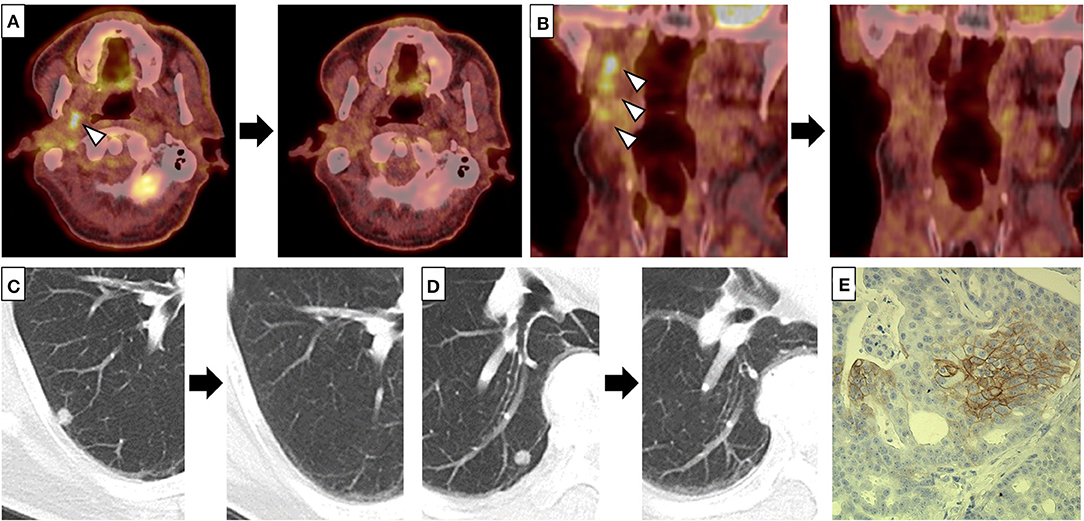

A 65-year old man noticed a cutaneous nodule on his left forearm, which had gradually grown. He had a medical history of diabetes mellitus and hypertension. The cutaneous nodule was resected, and was diagnosed to be malignant melanoma. He was referred to our hospital, and underwent wide resection with left axillar lymph node (LN) dissection. The surgical margin of the primary tumor was negative, and one out of the 11 dissected LNs showed metastases. 1 year after the surgery, computed tomography (CT) revealed a nodule in the right parotid gland. The nodule was resected, and histological analyses revealed multiple cysts of various sizes lined by cuboidal, eosinophilic cells with mild to moderate atypia (Figures 1A–C). The cyst lumen contained eosinophilic materials, and some of the cuboidal cells showed decapitation secretion (Figures 1A–C). There were no myoepithelial cells around the luminal cells. In some parts, the tumor cells showed microinvasion. From these findings, a diagnosis of cystadenocarcinoma was made. 4 months after the resection, a nodule with cystadenocarcinoma recurred in the right parotid gland, and right superficial parotidectomy was performed. The surgical margin was negative, and the patient received postoperative irradiation with 60Gy. At 4 and 6 years after the parotidectomy, resection was performed on two cutaneous nodules with metastatic melanoma that appeared on the left forearm (Figure 1D). PD-L1 expression level was <1%, and BRAF mutations were not detected. 9 years after the parotidectomy, positron emission tomography (PET)-CT revealed a 40 × 40 mm mass in the deep lobe of the right parotid gland with high fluorodeoxyglucose (FDG) accumulation (Figure 1E). In addition, multiple small nodules appeared in the lung. The mass in the parotid gland was resected, and histological analyses revealed multiple cysts with frequent papillary projection consisting of a proliferation of cuboidal cells with pleomorphism, indicating recurrent cystadenocarcinoma (Figure 1F). Tumor nests had invaded into the fibrotic stroma and multiple perineural invasions were also observed (Figures 1G,H). Because the mass had extended widely, it could not be completely excised and large parts of the surgical margin remained positive. 8 months after the last surgery, PET-CT revealed an irregularly shaped mass with high FDG accumulation below the surgical wound of the parotid gland (Figure 2A). In addition, right upper deep cervical LNs also showed high FDG accumulation (Figure 2B), indicating local recurrence and cervical LN metastases of cystadenocarcinoma. The size and number of lung nodules had also increased (Figures 2C,D). Because the lung nodules and the mass of recurrent cystadenocarcinoma appeared simultaneously, the nodules may be lung metastases of the cystadenocarcinoma. However, the lung nodules were also suspected to be metastatic melanoma because of the patient's medical history of lymph node and multiple skin metastases of melanoma. The patient would not agree to proposed partial lung resection for histological examination of the nodules. Therefore, based on our suspected diagnosis of lung metastases of melanoma, we proposed treatment with either anti-PD-1 antibody monotherapy or nivolumab and ipilimumab combination therapy. He selected the combination therapy, and was treated with combined nivolumab (80 mg/body) and ipilimumab (3 mg/kg) therapy. 2 weeks after the first administration of these antibodies, he developed Grade 4 liver injury, which required cessation of the treatment and a high-dose oral steroid with mycophenolate mofetil followed by steroid pulse therapy for improvement of the liver injury. However, PET-CT 4 months after the single course of the combination therapy showed that the FDG accumulation of both the mass below the surgical wound of the parotid gland and the cervical LNs had disappeared (Figures 2A,B). In addition, all of the lung nodules had disappeared (Figures 2C,D), suggesting that the combination therapy induced CR. At 10 months' follow-up after the immune checkpoint inhibitor (ICI) treatment, there was no recurrence.

Figure 2. (A–D) Fluorodeoxyglucose (FDG) accumulation of the mass below the surgical wound of the parotid gland (A) and right upper deep cervical lymph nodes (LNs) (B), and multiple lung nodules (C,D) disappeared after a single course of combined nivolumab and ipilimumab therapy. Left and right panels indicate positron emission tomography-computed tomography (PET-CT) (A,B) or CT (C,D) before and 4 months after a single course of combined therapy, respectively. Arrow heads indicate the mass below the surgical wound of the parotid gland (A) and the cervical LNs (B) with high FDG accumulation, respectively. (E) Some of the tumor cells of the recurrent cystadenocarcinoma were positive for PD-L1 (clone: sp142, ×200).

Programmed death ligand 1 (PD-L1) expression in SGC tumor cells is frequently observed, indicating that it may play an important role in the immune tolerance and progression of SGC (14). On examining PD-L1 expression, it was detected in more than 5% of the tumor cells of the recurrent cystadenocarcinoma although not in the metastatic melanoma (Figure 2E). In contrast, Ross et al. analyzed tumor mutation burden (TMB), which is known to be associated with favorable tumor response to ICIs, in 623 cases of SGC, and reported that the TMB of SGC was significantly lower than that of other tumor types for which ICIs were approved such as melanoma and breast cancer, although cases of cystadenocarcinoma were not included in this study (15). Consistently, recent studies demonstrated limited efficacy of anti-PD-1 monotherapy for advanced SGCs (16–18). However, there were no cases of cystadenocarcinoma within these studies, and there have been no reports of advanced cystadenocarcinoma of the salivary gland treated with ICIs. In our patient, the recurrent tumor of the parotid gland and cervical LN metastases of cystadenocarcinoma as well as the multiple lung nodules achieved CR with only a single course of combined nivolumab and ipilimumab therapy. Thus, our case suggests that ICIs, including combined therapy, could be a promising treatment for advanced cystadenocarcinoma.